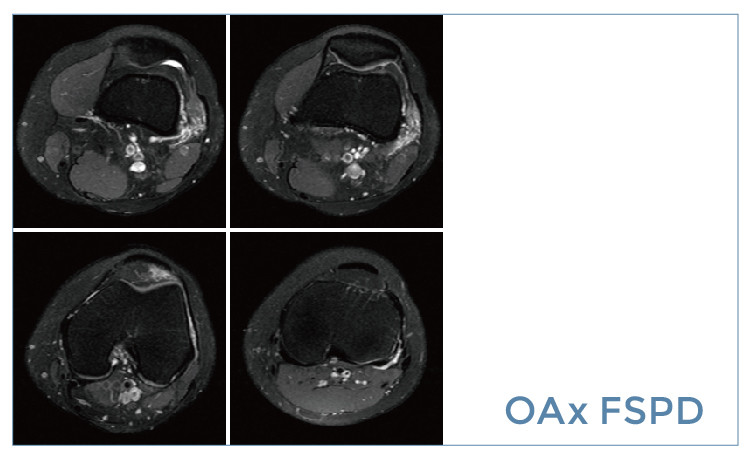

【朗润影像档案】磁共振影像病例分享(编号20190510)